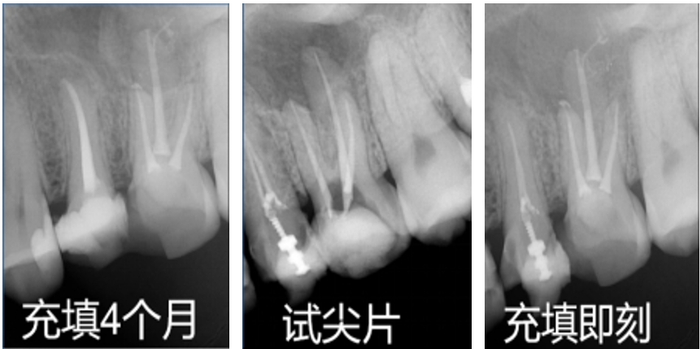

展会上,来自美国以及世界各地的众多根管医生驻足赛濡特展位,被C-Root SP进入牙本质小管,并在牙小管内形成锶代羟基磷灰石的根管再矿化电镜照片所震惊,在展位上观看了中国同行用硅酸锶糊剂C-Root SP充填的实操案例系列X线以及CBCT照片,现场试用C-Root SP根管充填糊剂,仔细观察外观颜色、颗粒细腻度,体验糊剂的流动性、粘稠度、饱和度等,连连感叹:中国的口腔生物陶瓷材料已经领先全球,当场登记申请马上试用。

数万个口腔医生用成功完美的充填案例,展示了C-Root SP五大优势,有图有真相,图片是世界性的语言,专业医生一看就懂——

l无与伦比的流动性 ,C-Root SP充填很丝滑!医生们现在很容易见到侧枝根管了!

l封闭性好:赛濡特C-Root SP的颗粒比较细,不仅能充填进细小侧枝根管,还可以进入牙小管(直径2-5微米)进行再矿化,形成锶代羟基磷灰石,起到有效的封闭作用。

l生物相容性好,术后反应小,患者无感。

l根尖周愈合快,充填长期效果显著。